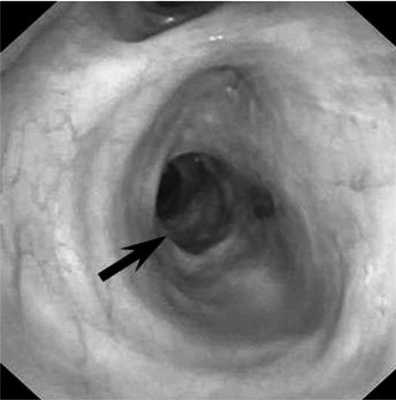

Пациент С., 28 лет, 29.07.14 был придавлен автомобилем к стене. Госпитализирован в ЦРБ г. Александрова, где при обследовании диагностирована тяжелая закрытая травма груди: множественные переломы ребер с двух сторон с разрывом легких, двусторонний пневмоторакс, правосторонний гемоторакс, подкожная эмфизема грудной клетки. Произведены правосторонняя торакотомия, ушивание разрывов верхней доли легкого, санация и дренирование правой плевральной полости, дренирование левой плевральной полости, диагностическая лапаротомия, ревизия органов брюшной полости. Через сутки (30.07.14) для дальнейшего лечения пациент переведен в НИИ СП им. Н.В. Склифосовского. При поступлении состояние больного тяжелое. Сознание - 10 баллов по шкале комы Глазго. Кожные покровы бледные, цианотичные. Искусственная вентиляция легких (ИВЛ) через оротрахеальную интубационную трубку. Грудная клетка равномерно участвовала в акте дыхания. Диагностирована двусторонняя подкожная эмфизема грудной клетки и шеи. Аускультативно дыхание жесткое, ослаблено с обеих сторон, больше справа. По дренажам из правой плевральной полости отмечено периодическое поступление воздуха. ЧСС 124 в минуту, АД 120/70 мм рт.ст. При рентгенологическом исследовании выявлена эмфизема мягких тканей грудной клетки с обеих сторон, переломы II-VII ребер справа и IV-VIII - слева, снижение прозрачности легочного поля в верхних и средних отделах правого легкого за счет контузионных изменений и кровоизлияний. При КТ-исследовании визуализированы множественные полисегментарные ушибы обоих легких с формированием гемопневматоцеле в нижней доле правого легкого, пневмомедиастинум, множественные переломы ребер и эмфизема мягких тканей передней грудной стенки. При фибробронхоскопии (ФБС) через интубационную трубку в просвете трахеобронхиального дерева, больше справа, выявлено значительное количество крови и сгустков. Выполнена санация просвета трахеи и бронхов раствором диоксидина 0,01% 60 мл. Сгустки крови удалены. В промежуточном бронхе визуализирован сгусток крови длиной 20-25 мм, занимающий 2/3 просвета бронха. По латеральной стенке бронха, не прикрытой сгустком крови, определялся дефект стенки бронха. При проведении аппарата дистальнее сгустка визуализировали среднедолевой и нижнедолевой бронхи. При ФБС, выполненной через 12 ч, в просвете бронхов определяли умеренное количество слизистого секрета с примесью крови. На 5 мм дистальнее карины по заднемедиальной стенке правого главного бронха выявлен дефект стенки 10 мм в диаметре с рваными краями и с образованием полости диаметром 10-15 мм (рис. 1). Правый верхнедолевой бронх не изменен, сегментарные бронхи проходимы. На расстоянии 10 мм от шпоры правого верхнедолевого бронха и на уровне верхнего края устья среднедолевого бронха визуализирован циркулярный разрыв стенки промежуточного бронха с диастазом краев 20-25 мм (рис. 2). Средне- и нижнедолевые бронхи правого легкого не изменены. Таким образом, локализация разрывов бронхов не позволяла исключить правостороннюю пневмонэктомию как возможный объем операции. Однако вмешательство с раздельной интубацией бронхов и выключением правого легкого на фоне массивной контузии левого легкого, выраженной легочной недостаточности и постгипоксического синдрома представлялось крайне рискованным. В связи с полным расправлением легких, отсутствием значительного сброса воздуха по дренажам из плевральной полости и нарастающей эмфиземой на фоне ИВЛ решено воздержаться от операции и выбрать консервативную тактику. Проводили комплексную интенсивную терапию: ежедневные двукратные санационные ФБС; антибиотикопрофилактика (цилапенем 4000 мг/сут в/в, метронидазол 1000 мг/сут в/в); переливание иммуноглобулина 100 мл в/в, 2 доз эритроцитной массы и 11 доз свежезамороженной плазмы крови, 100 мл/сут 10% альбумина; муколитическая, ингаляционная, противовоспалительная терапия. На 2-е сутки наложена трахеостома для продленной ИВЛ.

Рис. 2. Циркулярный разрыв промежуточного бронха. 1 - проксимальный край диастаза циркулярного разрыва; 2 - диастаз краев циркулярного разрыва; 3 - дистальный край диастаза циркулярного разрыва.